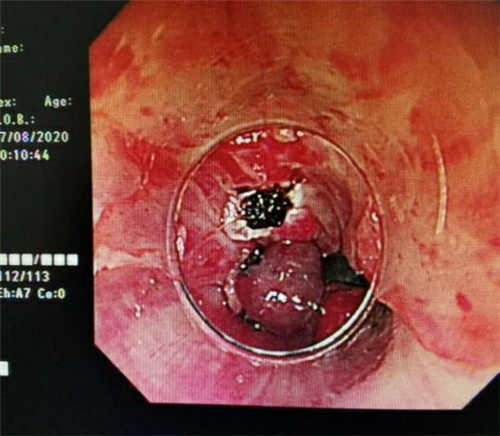

手术中,在镜下发现数条食管静脉曲张延伸至胃底,胃腔内有大量新鲜红色血液及血凝块,寻找到出血部位时仍在向外渗血,血压持续下降,患者时刻有生命危险。曹鹏副主任当机立断对曲张静脉破口处进行组织粘合剂及硬化剂注射,并对曲张静脉进行套扎治疗,在麻醉师陈琦的保驾护航下,整个过程不到半个小时,为患者成功止血,患者转危为安。